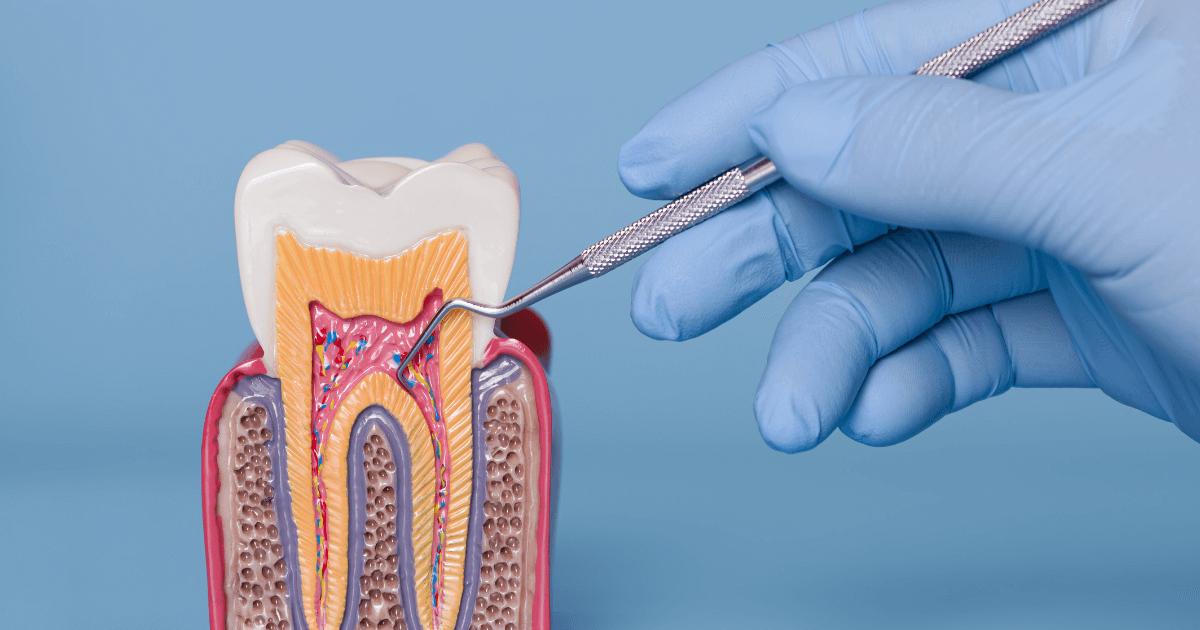

歯の構造

歯は3つの層からできています。いちばん外側のエナメル質は硬い殻で、むし歯や力から内側を守ります。中間の象牙質には細い管が走り、冷たい物や甘い物の刺激が神経へ伝わりやすい層です。中心の歯髄には血管と神経が通り、炎症で腫れると内圧が上がってズキズキした拍動痛が出やすくなります。

歯の根の先は歯根膜というクッションで骨に支えられ、噛む力を分散します。力が一部の歯だけに偏ると歯根膜が炎症に傾き、噛んだ瞬間だけ鋭い痛みが出ることがあります。

しみる短い痛みは表層のトラブル、何もしなくても続く痛みは深い炎症が候補、噛んだときだけの痛みは力の問題が原因になるでしょう。